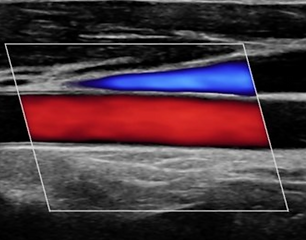

Knowledge of vascular anatomy and physiology gives participants the skills to assess and detect abnormalities, increase their diagnostic confidence and provide a higher quality of care.

Hello, my name is Erin Veasey. I’m a RDMS & RVT sonographer with two decades of experience working as a clinical sonographer, teacher and educational specialist. I’ve worked in both general imaging departments and vascular labs performing abdominal, OB/GYN, small parts, MSK, and vascular ultrasound exams. As the founder of Esonography, LLC. my passion is helping educate sonographers to enhance and improve their practice. This vascular ultrasound online course is designed specifically for registered sonographers who are interested in professional development, additional credentials, and providing a high standard of patient care. It’s intended to give sonographers clinical confidence while preparing participants to sit for the vascular technology exam.